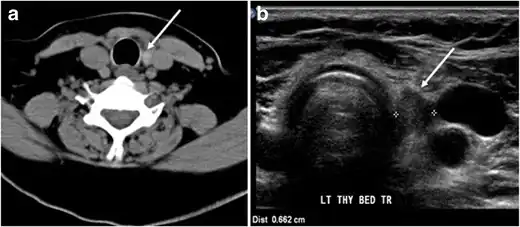

Fig. 7. A 51-year-old female patient post total thyroidectomy for PTC with elevated thyroglobulin measurement. an Axial non-enhanced CT scan of the neck at the level of the thyroid bed demonstrates a well-defined, rounded, homogenously dense soft tissue situated between the trachea and left internal jugular vein (white arrow). b Transverse ultrasound image of the neck demonstrates a well-defined, homogeneous, hypoechoic soft tissue nodule measuring 6 mm (white arrow) with no detected micro-calcifications. Biopsy showed a predominantly residual normal thyroid tissue with micro-foci of PTC.[1] -